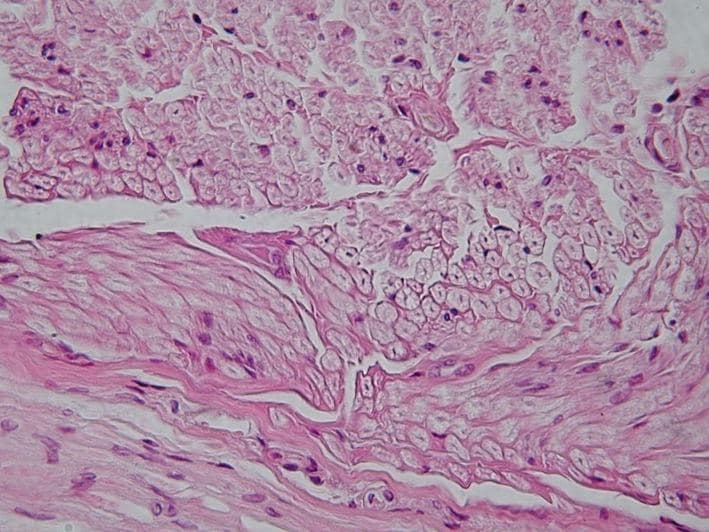

Un tissu en biologie est le niveau d'organisation intermédiaire entre la cellule et l'organe. Un tissu est un ensemble de cellules semblables et de même origine, regroupées en amas, réseau ou faisceau (fibre). Un tissu forme un ensemble fonctionnel, c'est-à-dire que ses cellules concourent à une même fonction. Les tissus biologiques se régénèrent régulièrement et sont assemblés entre eux pour former des organes. La science qui étudie les tissus est l'histologie. Il existe plus d'une centaine de tissus chez les animaux. Tous sont regroupés en quatre grandes catégories selon leur morphologie : le tissu épithélial est un ensemble de cellules serrées les unes aux autres formant un ensemble avasculaire mais innervé, séparé d'un tissu conjonctif sous-jacent par une structure de soutien appelée lame basale. Ce type de tissu est dit de revêtement lorsqu'il se retrouve sur les surfaces qui jouxtent le milieu externe ou les cavités de l'organisme. Il est appelé glandulaire lorsqu'il est regroupé en structure spécialisée dans la production de sécrétion ou d'hormone. Le tissu épithélial dérive essentiellement de l'endoderme et de l'ectoderme, et dans une faible part du mésoderme ; le tissu conjonctif dont les cellules sont disjointes, séparées par des matériaux extracellulaires, désigne une large gamme de tissus. On trouve dans cet ensemble le sang, le squelette des vertébrés, les couches profondes de la peau, etc. Il a en général un rôle de soutien. Le tissu conjonctif dérive du mésoderme ; le tissu musculaire est formé de cellules contractiles et permet le mouvement. Il dérive du mésoderme ; le tissu nerveux est formé de cellules polarisées agencées en réseau et permet le contrôle du fonctionnement de l'organisme. Il dérive de l'ectoderme. Sur le plan embryonnaire, les tissus conjonctifs proviennent du mésoderme. Ils sont donc présents uniquement chez les animaux triploblastiques. Chez les animaux diploblastiques (éponges, méduses, coraux), les deux tissus de bases (ectoderme et endoderme) sont séparés par la mésoglée, une gelée acellulaire, et les fonctions des tissus conjonctifs sont partiellement prises en charge par l'ectoderme.